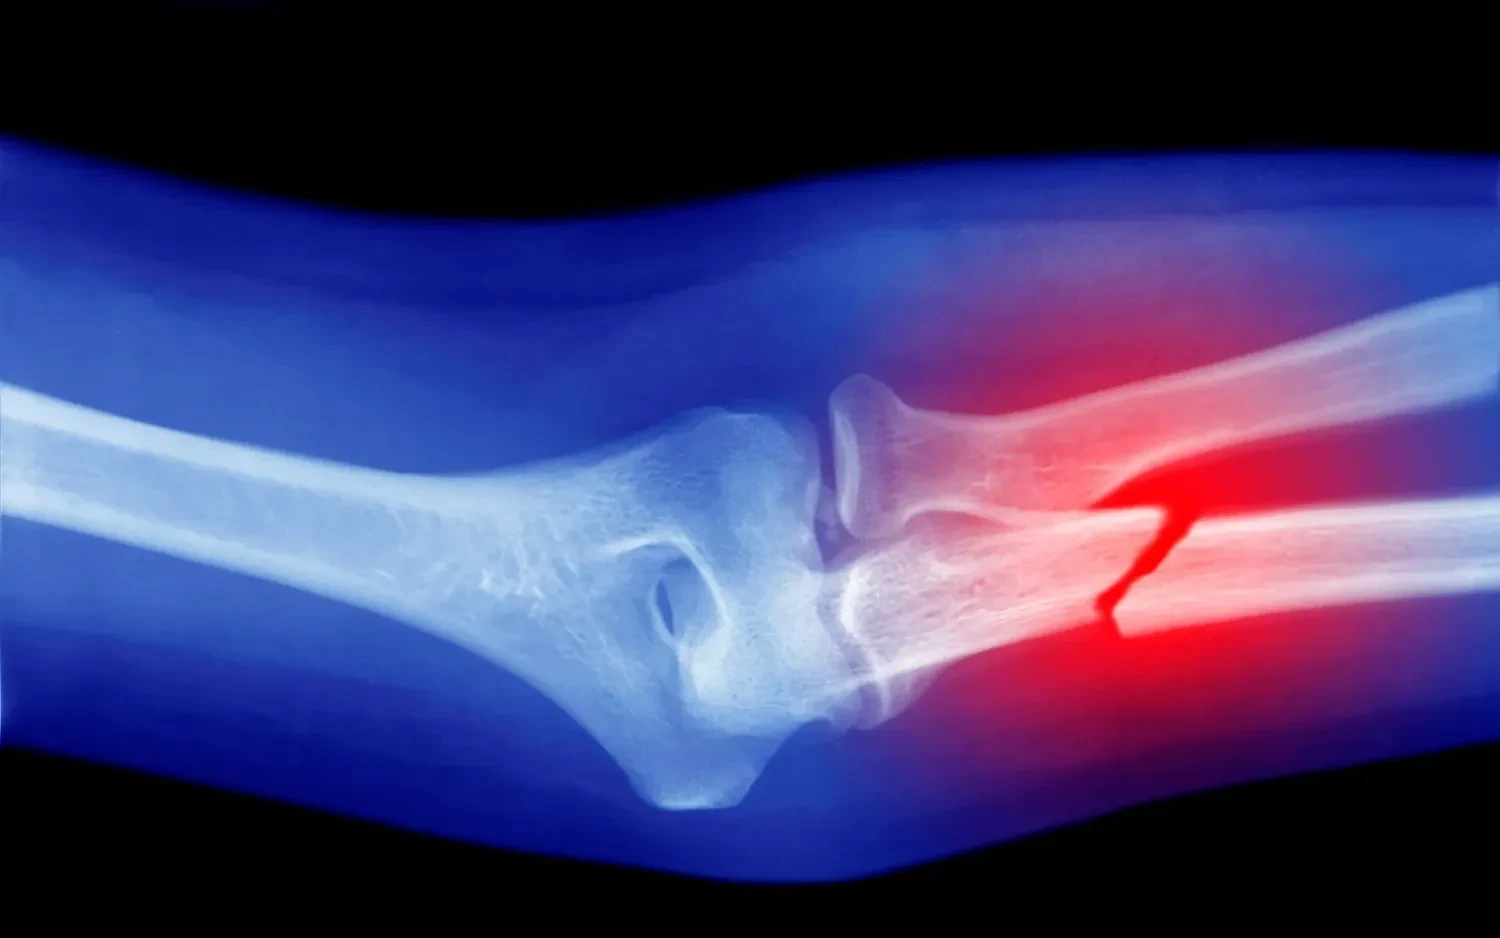

Огляд понад 60 наукових робіт довів: мікропластик, потрапляючи в організм, може впливати на клітини кісткової тканини та сприяти розвитку остеопорозу. Вчені виявили, що пластикові частинки стимулюють утворення остеокластів – клітин, які руйнують кісткову тканину, порушуючи природний баланс відновлення кісток. Про це повідомляє видання Wired із посиланням результати досліджень, опубліковані у журналі Osteoporosis International, пише УНН.

Протягом життя кістки постійно оновлюються, але при остеопорозі руйнування відбувається швидше, ніж регенерація. Новий аналіз, опублікований у журналі Osteoporosis International, додає мікропластик до списку факторів ризику цієї хвороби поряд із віком, генетикою, дієтою чи шкідливими звичками.